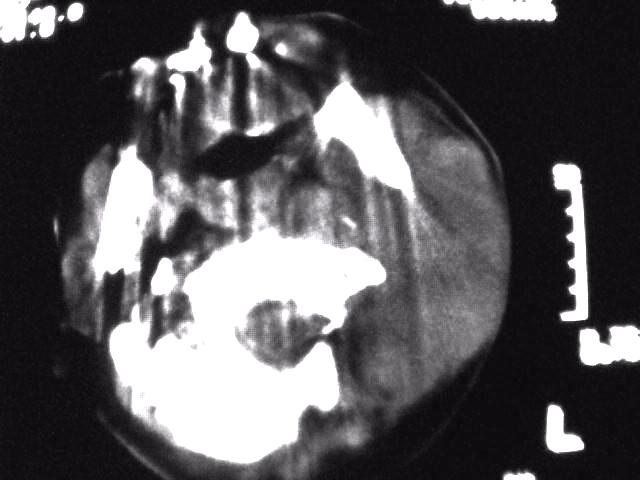

颈部层厚10mm间距10mm连续扫描及增强扫描共24层示:左侧下颈部胸锁乳突肌内侧区域内可见多发软组织结节,密度不均,内可见斑片状低密度区,大小不等,部分融合成块,左侧融合成一块者大约9.0x5.4,与周围肌肉、血管等结构界面不清,骨质未见明显浸润影。左侧锁骨下可见多个软组织结节,与周围界限尚清,左侧锁骨上窝内可见一大软组织肿物,大小约4.7x3.7cm,内密度欠均匀中心可见低密度区。

考虑:左侧颈部及双侧锁骨下多发淋巴结肿。非何杰金氏淋巴瘤可能性大,建议进一步检查。